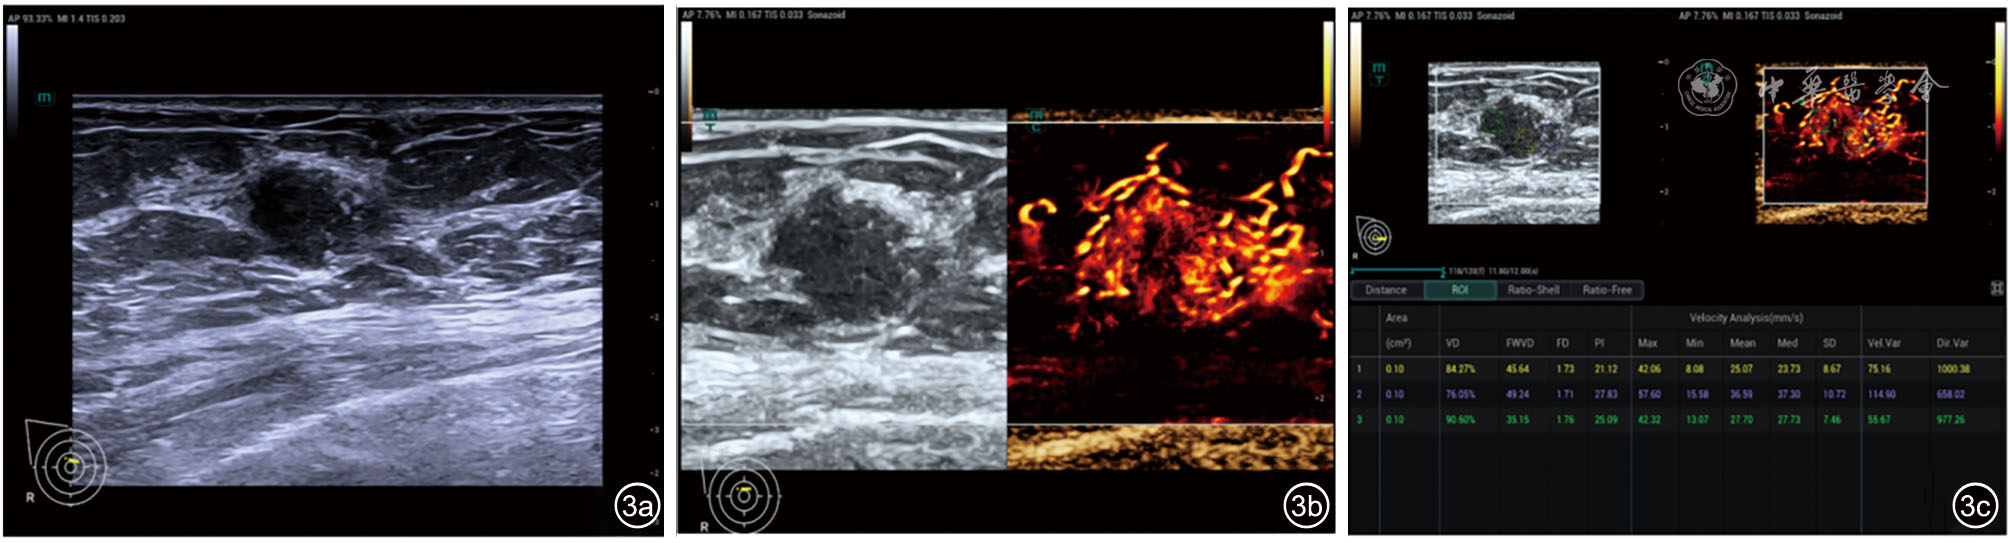

We enrolled 132 patients with pathologically confirmed invasive breast cancer (55 HER-2 positive, 77 HER-2 negative) from the Second Hospital of Shanxi Medical University between March and September 2025. All patients underwent preoperative B-mode ultrasound and SR-CEUS examinations. Predictors were screened through univariate and multivariate logistic regression analyses. Three predictive models were constructed: Model 1 (clinical parameters + B-mode ultrasound features), Model 2 (SR-CEUS characteristics alone), and Model 3 (clinical parameters + B-mode ultrasound features + SR-CEUS characteristics). A nomogram was developed based on Model 3. Internal validation was performed using the bootstrap method. Model performance was assessed via receiver operating characteristic (ROC) curves, with area under the curve (AUC) differences compared using DeLong test. Calibration curves and the Hosmer-Lemeshow test were used to evaluate calibration and goodness-of-fit, while decision curve analysis (DCA) was performed to quantify clinical decision benefit.

Univariate analysis revealed significant associations between HER-2 status and estrogen receptor (ER), progesterone receptor (PR), calcification, perfusion defects, vascular density, flow weighted vessel density (FWVD), perfusion index (PI), and blood flow velocity (OR=0.174, 0.149, 3.399, 2.837, 1.085, 1.104, 1.231, 1.081, all P<0.05). Multivariate analysis identified PR negativity (odds ratio [OR]=0.211), calcification (OR=2.553), perfusion defects (OR=3.469), FWVD (OR=1.088), and PI (OR=1.184) as optimal predictors. The AUC values for Models 1, 2, and 3 in predicting HER-2 positive breast cancer were 0.763, 0.832, and 0.880, respectively. The combination model (Model 3) demonstrated a significantly higher AUC than Model 1 (P<0.001) and Model 2 (P=0.039). Internal validation confirmed model stability. Calibration curves and the Hosmer-Lemeshow test indicated good calibration and fit. DCA showed superior net clinical benefit across a wide threshold probability range for the combination model.